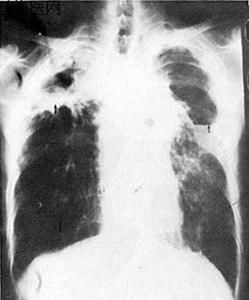

肺結核有五種病灶,如鈣化病灶、滲出性病灶、乾酪樣病灶、增殖性病灶、纖維性病灶,不同的病灶有不同的X線徵象。

肺結核病的X線像有以下特徵:

(1)鈣化病灶:外形一般不規則,中間有點狀的顆粒陰影。密度最深,邊緣清楚。

(2)滲出性病灶:雲霧狀、呈彌散性,有密度較高的中心灶,整個病灶周圍邊緣不整齊。

(3)乾酪樣病灶:密度較高,均勻、液化時見空洞。

(4)增殖性病灶:小者如帽針頭,大者如黃豆大,邊緣清楚整齊,密度深,大小不一。

(5)纖維性病灶:條狀收縮,周邊肺氣腫。